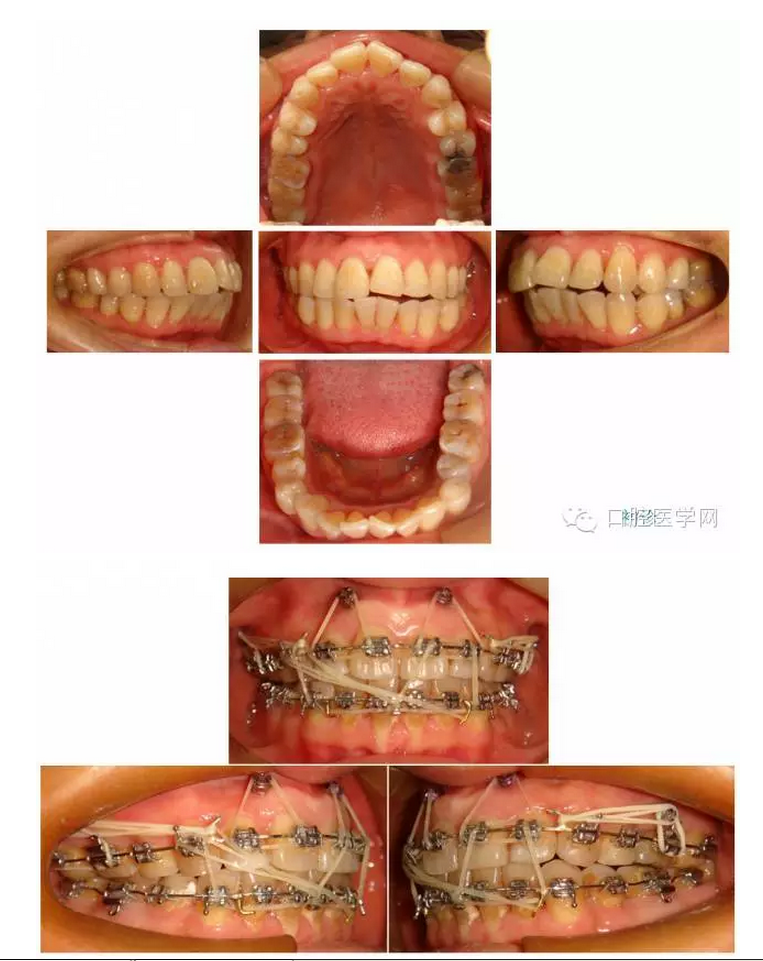

口腔衛(wèi)生不良患者正畸期間口腔衛(wèi)生會進一步下降,加重牙體及牙周損害。因此應(yīng)該作為禁忌癥。如果家長急于矯治,需要對患者進行口腔衛(wèi)生指導(dǎo)及管理。如果能夠達到保持口腔衛(wèi)生良好1個月以上,可以開始矯治。

很多牙周病患者口腔衛(wèi)生口腔衛(wèi)生比較差,矯治前應(yīng)該進行系統(tǒng)的牙周治療及口腔衛(wèi)生管理,達到牙周病穩(wěn)定及口腔衛(wèi)生良好3個月以上,可以考慮開始矯治。即使這樣一部分患者矯治期間口腔衛(wèi)生可能下降,牙周病可能加重,就像我的這一例患者。這種情況復(fù)診時要經(jīng)常檢查督促,必要時要轉(zhuǎn)牙周科進行牙周治療。